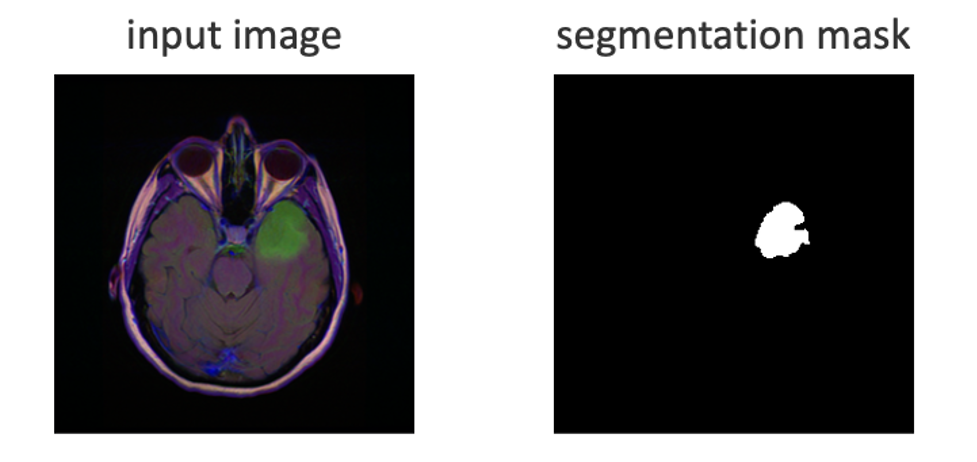

Let’s consider the problem of training a neural network for object recognition in a supervised setting. Specifically, we adapt the code available publicly here. The goal is to identify abnormal brain tissue in magnetic resonance images (MRI), given matching “segmentation masks” that indicate the desired solution.

In the Figure 1, Input image on the left is an MRI slice of a human head. Input image on the right shows a lesion highlighted in upper right. The segmentation mask on the right uses pixels 0 or 1 to mark the lesion shape and location.

Figure 1 – Input datum represented by an enhanced MRI image and matching mask of the lesion area.